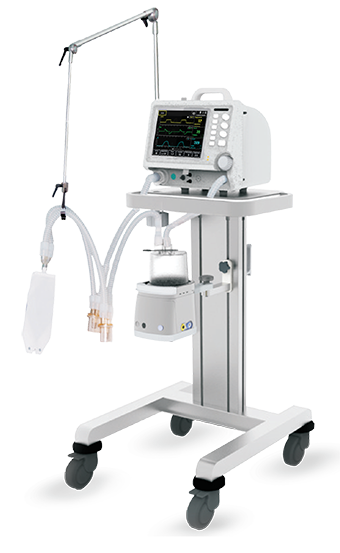

Transport Ventilators - vent I

Transport Ventilators - vent I

Portable ICU Ventilator Optima

Portable ICU Ventilator Optima

Astral Ventilator - Rental

Astral Ventilator - Rental

EMERGENCY VENTILATOR

EMERGENCY VENTILATOR

BMC G2S B25VT BiPAP ST WITH HUMIDIFIER AND MASK

BMC G2S B25VT BiPAP ST WITH HUMIDIFIER AND MASK

Astral 150 Portable Ventilator

Astral 150 Portable Ventilator